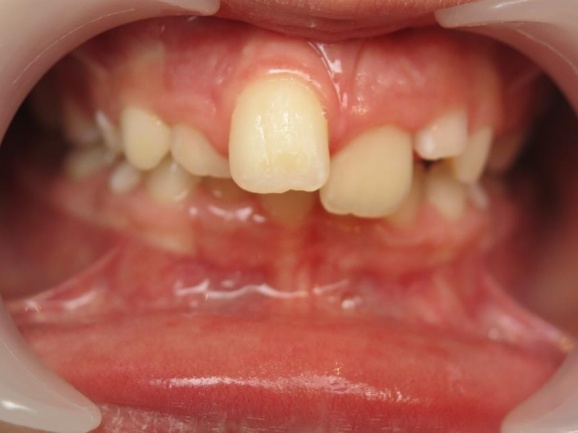

2 - Phase 1: Correction du décalage des mâchoires

Ce type de traitement, au résultat visuellement impressionnant, n’est possible que lorsque le problème vient du maxillaire supérieur trop en avant. Si c’est au contraire la mâchoire inférieure qui n’a pas assez grandi, le traitement est plus complexe et nécessite souvent une approche combinée orthodontie-chirurgie.